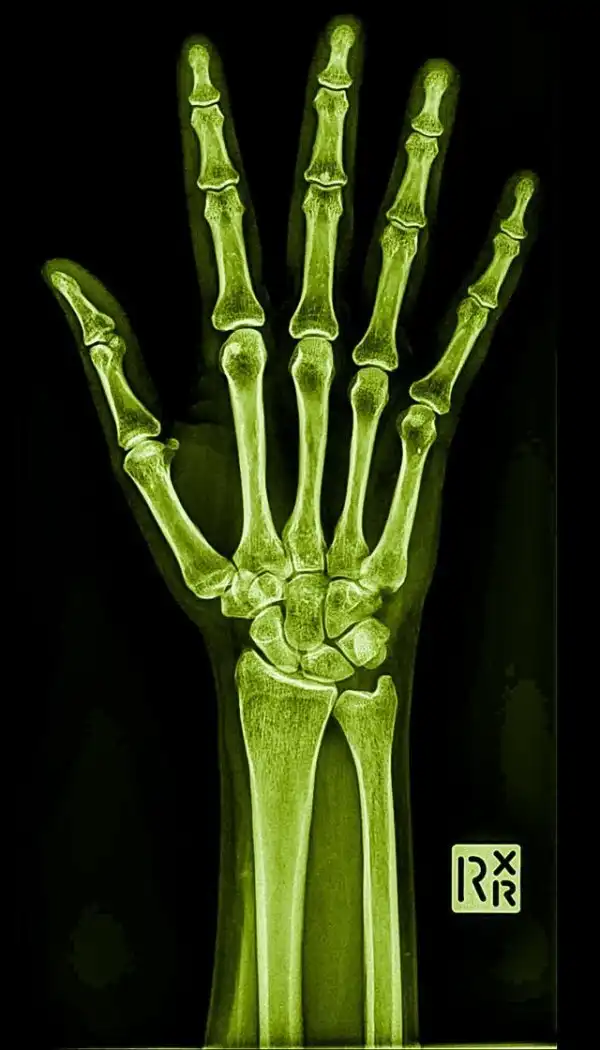

Рука пианиста, который играет 30 лет